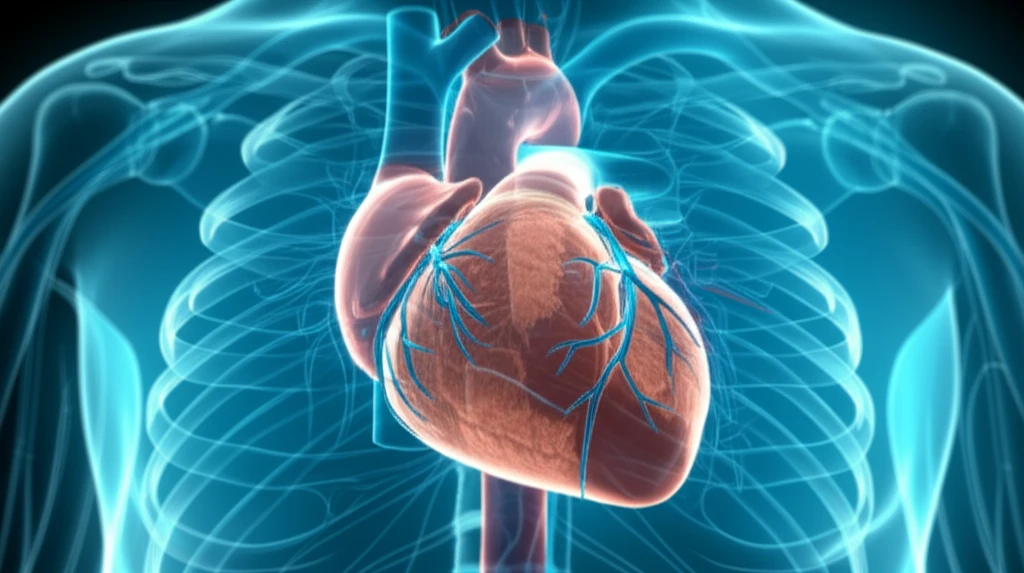

Ventricular tachycardia (VT), a rapid and erratic heartbeat originating in the heart's ventricles, can be life-threatening. Radiofrequency ablation, a common procedure to treat VT, isn't always successful, especially when the source of the arrhythmia lies deep within the heart muscle – a condition known as intramural VT. These deeply seated foci are hard to reach and eliminate with conventional methods, leading to recurrence and the need for repeated interventions.

When standard ablation fails, doctors sometimes turn to transcoronary ethanol ablation (TCEA). This involves injecting ethanol, a type of alcohol, into small coronary arteries that feed the problematic area of the heart, creating a targeted lesion to disrupt the abnormal electrical pathways. However, accurately targeting these arteries is crucial for the procedure's success and to avoid complications.

The key innovation explored in this study is the use of advanced imaging techniques before the TCEA procedure. Researchers utilized cardiac magnetic resonance (CMR) and computed tomography (CT) scans to map the heart's structure, identify the precise location of the intramural VT source, and visualize the network of coronary arteries in relation to this source. This detailed roadmap allows doctors to plan the TCEA procedure with much greater accuracy.